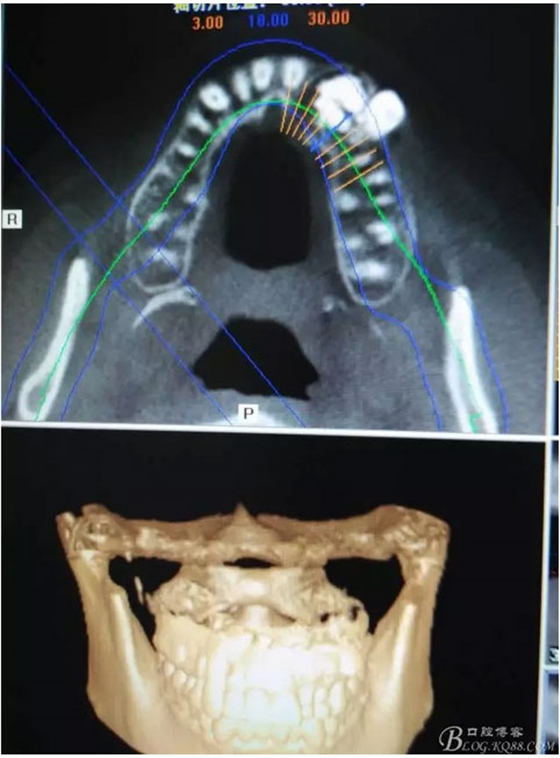

圖1。術(shù)前的CBCT影像檢查:22位于鼻底下方,23位于24、25的根方。左側(cè)乳Ⅱ、Ⅲ根方顯示囊性改變,囊腔內(nèi)大量致密鈣化團(tuán)塊,密度高。